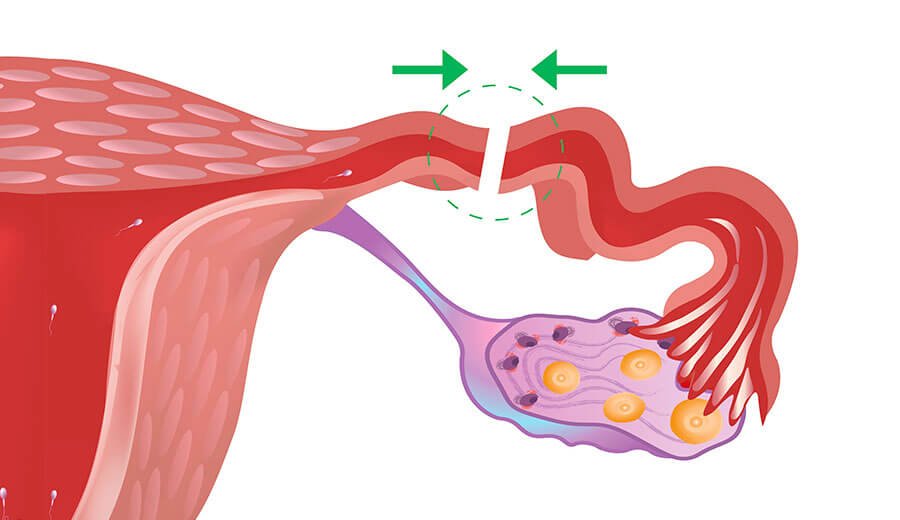

Laqueadura tubaria

Procedimento cirúrgico no qual as trompas de falópio são bloqueadas para prevenir a gravidez. É uma opção segura e eficaz para mulheres que não desejam ter filhos no futuro.

A reversão de laqueadura, também conhecida como recanalização tubária, consiste em desfazer a obstrução ou reconectar as trompas, permitindo o fluxo de óvulos dos ovários para o útero, possibilitando a concepção natural.